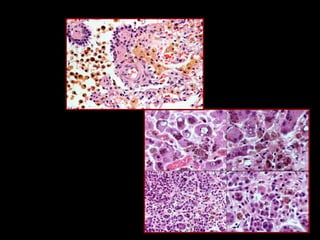

ACUMULACIÓN DE PROTEÍNAS

1. Cuerpos de Mallory: son queratinas acumuladas

(filamentos intermedios)

2. Se observa en los hepatocitos de alcohólicos, se dañan los

filamentos intermedios y se acumulan intracelularmente

Cuerpos de Mallory en el hígado

Acumulaciones de alpha-1-antitrypsin

teñidas con PAS en hígado